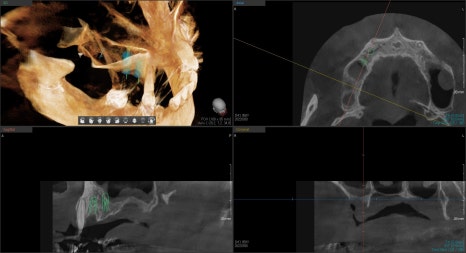

물론 수술 전 3D CT를 통해 정확한 진단이 우선시 되어야 합니다.

3D CT를 찍어 진단을 더 디테일하게 진행했습니다.

위턱뼈의 경우 양쪽의 상악동 거상술이라는 방법으로 부족한 뼈의 양을 만들어주었고,

아래턱뼈의 경우는 치조골 이식술을 통해 흡수된 볼륨을 회복시켜주는 치료를 했습니다.